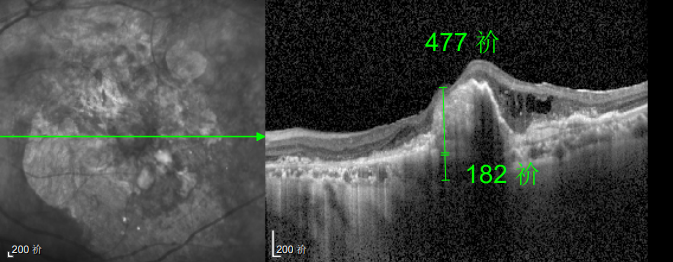

△規(guī)劃化治療后的左眼

對此,王曉波主任再次強調了抗 VEGF 治療的核心規(guī)范:“初始治療期的3針是關鍵,能為病情控制打下基礎,絕不能因視力暫時改善就中斷;后續(xù)必須每1-3個月復查一次,醫(yī)生會根據眼底情況調整鞏固方案,病情穩(wěn)定者可延長至半年,但絕對不能自行停藥。”

幸運的是,三年后的一次例行復查中,醫(yī)生通過眼底監(jiān)測及時發(fā)現林婆婆的右眼眼底病變問題,確診為濕性老年性黃斑變性。得益于定期篩查的及時性,王曉波主任第一時間為她啟動治療,最終成功將右眼矯正視力穩(wěn)定在0.8左右。